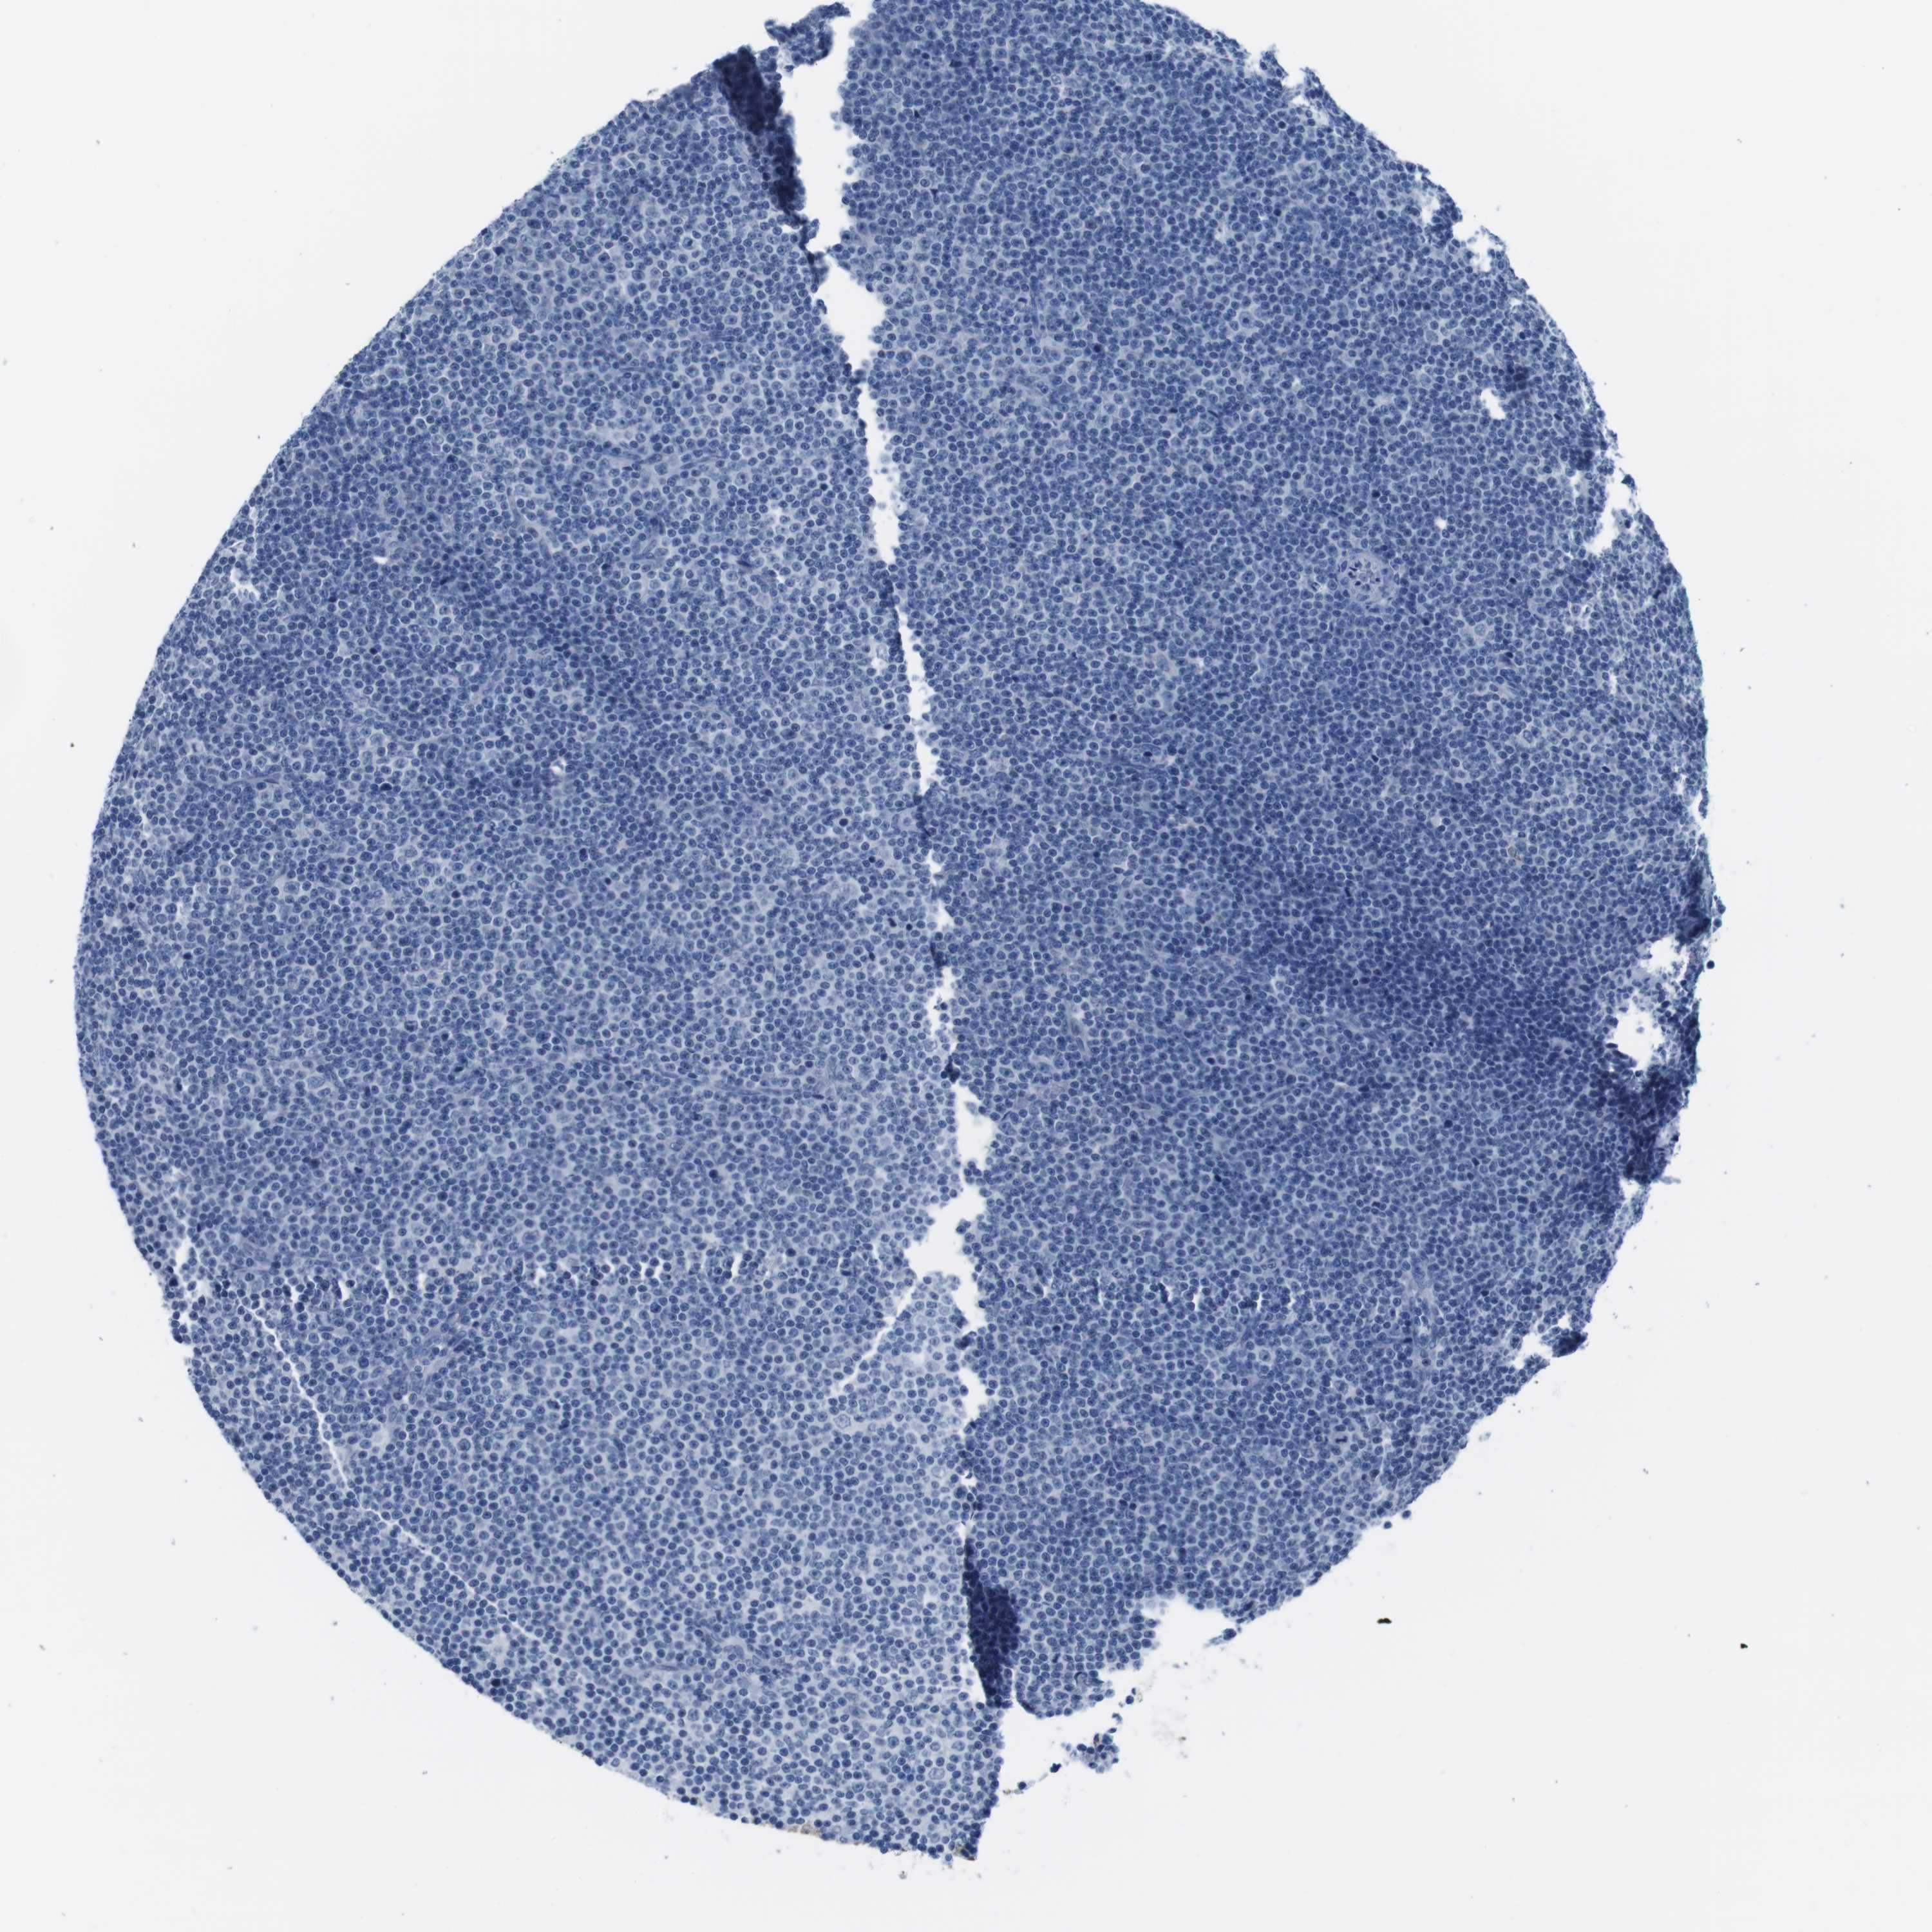

CANCER LYMPHOMA Show tissue menu

LYMPHOMA - Protein expressioni

A mouse-over function shows sample information and annotation data. Click on an image to view it in a full screen mode. Samples can be filtered based on level of antibody staining by selecting one or several of the following categories: high, medium, low and not detected. The assay and annotation is described here.

Each image is clickable and will lead to virtual microscopy that enables deeper exploration of all samples and also displays staining intensity scores, fraction scores and subcellular localization as well as patient and tissue information for each sample.

Antibody HPA039061

Antibody HPA039062

Antibody CAB015442

Antibody CAB022600

Hodgkin's disease, NOS

Malignant lymphoma, non-Hodgkin's type, High grade

Malignant lymphoma, non-Hodgkin's type, Low grade